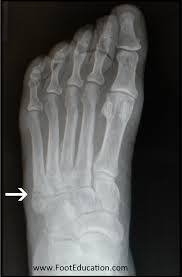

The sutures in the small incision will need to be removed after 10 to 14 days. See more ideas about fracture healing, jones fracture, fracture. These are notorious for very slow healing. What is the recovery time of a broken ankle? Do you have a jones fracture of the 5th metatarsal? Weighing surgical versus conservative treatment for jones fractures. Well find out exactly how to get this bone feeling better! This is an ap view of a percutaneous jones fracture surgery. Outside of the foot pain can be improved with a few simple treatment. While people can relate to a stubbed toe or sprained ankle; Surgical treatment of femoral neck fracture. 5th metatarsal fracture recovery time: A jones fracture occurs in a region known as the the incision required to repair a jones fracture is small and the surgery can be done as an outpatient procedure under general or local anesthesia.

They occur at the intersection between the base and the shaft of the fifth metatarsal. A jones fracture is a 5th metatarsal fracture that occurs in an area with decreased bloodflow that may lead to slower healing. Femoral neck fracture — pathophysiology and recovery time. It results in pain near the midportion of the foot on the outside. Surgery is almost always necessary to treat a fractured femur.

Intramedullary Screw Fixation Of Proximal Fifth Metatarsal Fractures In Athletes from www.scielo.br Lengthy healing times and risk of refracture may be reasons for surgical repair in these fractures. A foot can be broken in many places learn about the jones fracture, what types of treatments are available, and if jones fracture surgery is the best treatment option. Patient may be in a removable boot after surgery for a week or two at the direction of the physician. Jones fractures are named after sir robert jonestrusted source , an orthopedic surgeon who in 1902 reported on his own injury and the injuries of several people he. Do you have a jones fracture of the 5th metatarsal? Jones fracture surgery recovery on mainkeys. A jones fracture is a break between the base and middle part of the fifth metatarsal of the foot. Yet surgery is not always necessary.

A jones fracture is a break between the base and middle part of the fifth metatarsal of the foot. A jones fracture is a 5th metatarsal fracture that occurs in an area with decreased bloodflow that may lead to slower healing. Remember that below is a guide to recovery and that everyone heals at different rates and some people do take longer. Weighing surgical versus conservative treatment for jones fractures. Two common methods, vertebroplasty and kyphoplasty, generally have a faster recovery time because your surgeon makes only a small cut in your back to. Zone 2 fractures are known as jones fractures. Well find out exactly how to get this bone feeling better! Have foot pain at some time in their lives. What is a lisfranc fracture? Jones fracture surgery recovery on mainkeys. This is another way of saying a jones fracture. Sanders type 3 break with surgery about 1 week later. It can take time to heal because there is limited blood flow to the area.